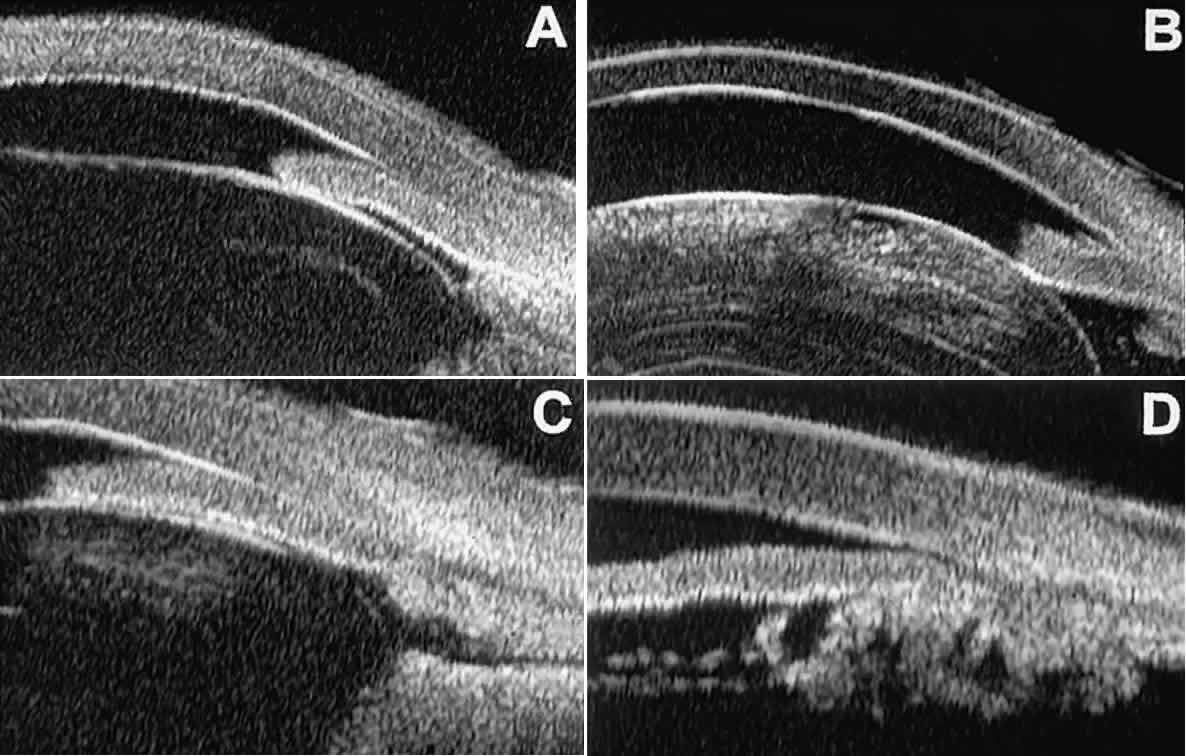

of the angle. In open-angle glaucoma, UBM can be used to measure the anterior chamber

angle in degrees, to assess the configuration of the peripheral iris, and

to evaluate the trabecular meshwork (Fig. 9).2,4 The angle configuration can be graded and compared with gonioscopic findings. In

certain patients with open-angle glaucoma, UBM can provide

information that may be of some diagnostic value (Fig. 10). For example, in pigment dispersion syndrome (see Fig. 10A),6 UBM typically reveals posterior bowing of the peripheral iris (“q” configuration

of peripheral iris by Spaeth classification5). In plateau iris syndrome (see Fig. 10B),7 UBM usually reveals abnormally steep anterior angulation of the peripheral

iris (“s”configuration of peripheral iris by Spaeth classification5), insertion of the iris from the anterior ciliary body, and retroiridic

projection of the ciliary processes. In eyes with peripheral anterior

synechiae (see Fig. 10C and D), UBM can reveal the extent of iridocorneal adhesion even if the cornea

is hazy or opaque.  Fig. 9. Angle configuration in eyes with open-angle glaucoma. A. Wide open angle with flat iris plane (D40r configuration by Spaeth gonioscopic

grading system). B. Moderately wide angle with anteriorly bowed iris plane (C30r by Spaeth

gonioscopic grading system). Fig. 9. Angle configuration in eyes with open-angle glaucoma. A. Wide open angle with flat iris plane (D40r configuration by Spaeth gonioscopic

grading system). B. Moderately wide angle with anteriorly bowed iris plane (C30r by Spaeth

gonioscopic grading system).

|

Fig. 10. UBM features of special glaucoma cases. A. Pigment dispersion syndrome with posterior bowing of peripheral iris (“q” configuration by Spaeth gonioscopic grading system). B. Plateau iris syndrome with origin of iris from anterior surface of ciliary

processes behind peripheral iris, slitlike narrowing of peripheral

angle, and abrupt transition from steep peripheral iris to flat iris

midzone. C. Broad peripheral anterior synechia with posterior bowing of nonadherent

iris. D. Peripheral anterior synechia with aqueous-filled slit between site of

iridocorneal adhesion and iris root after cataract extraction with implantation

of posterior-chamber IOL. Fig. 10. UBM features of special glaucoma cases. A. Pigment dispersion syndrome with posterior bowing of peripheral iris (“q” configuration by Spaeth gonioscopic grading system). B. Plateau iris syndrome with origin of iris from anterior surface of ciliary

processes behind peripheral iris, slitlike narrowing of peripheral

angle, and abrupt transition from steep peripheral iris to flat iris

midzone. C. Broad peripheral anterior synechia with posterior bowing of nonadherent

iris. D. Peripheral anterior synechia with aqueous-filled slit between site of

iridocorneal adhesion and iris root after cataract extraction with implantation

of posterior-chamber IOL.